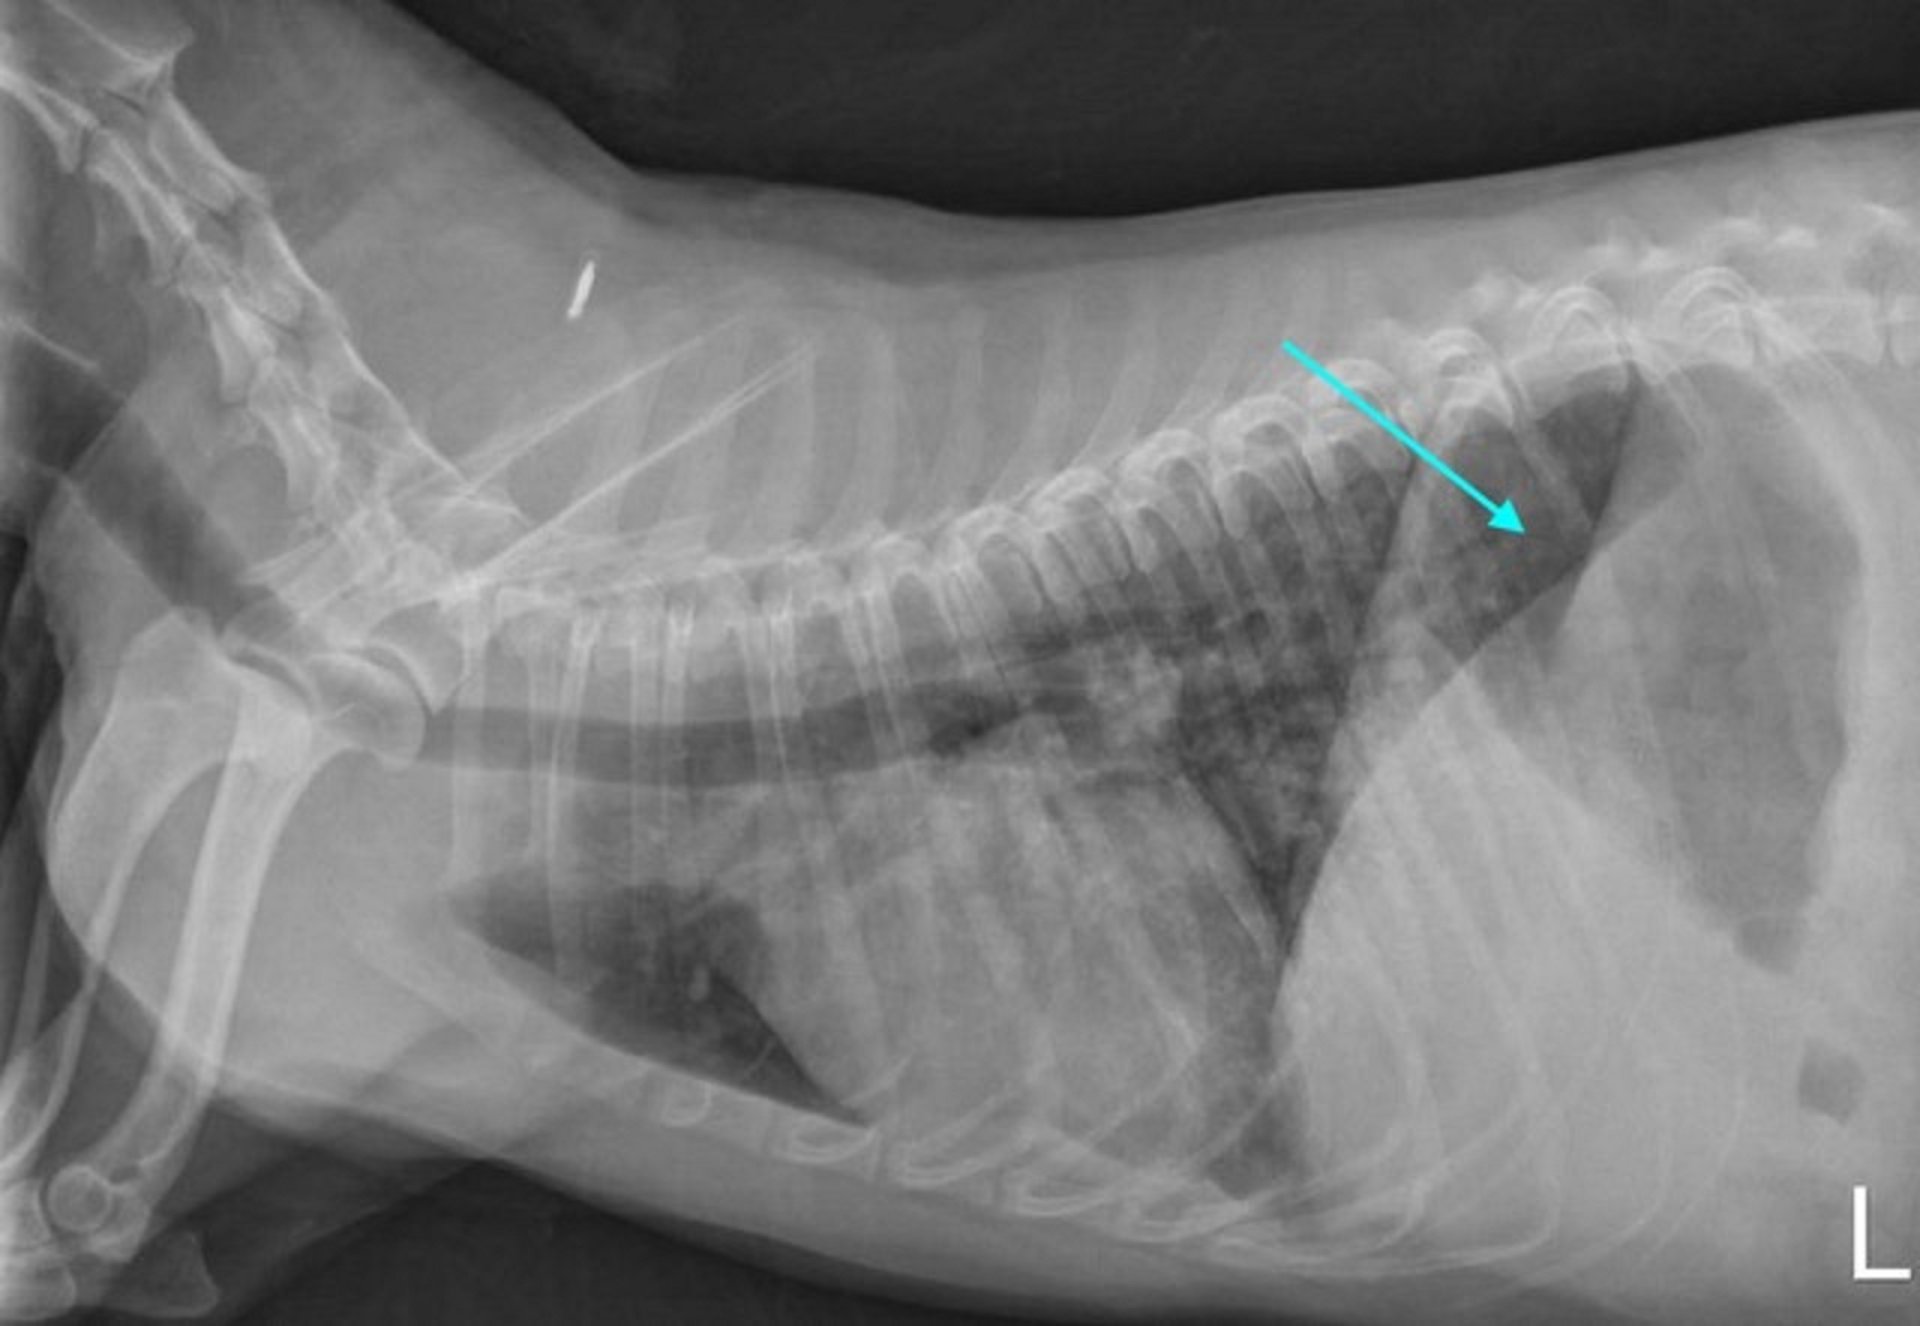

胸部 X 线片可能显示弥漫性或尾背网状结节性肺混浊,可能是由于肺出血。 腹部 X 线片可能正常,也可能显示肾肿大或肝肿大。

由 Katharine F. Lunn 博士友情提供。